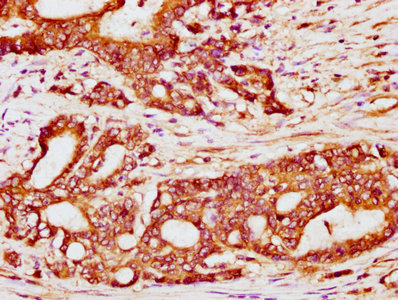

IHC image of CSB-PA882156LA01HU diluted at 1:200 and staining in paraffin-embedded human small intestine tissue performed on a Leica BondTM system. After dewaxing and hydration, antigen retrieval was mediated by high pressure in a citrate buffer (pH 6.0). Section was blocked with 10% normal goat serum 30min at RT. Then primary antibody (1% BSA) was incubated at 4°C overnight. The primary is detected by a biotinylated secondary antibody and visualized using an HRP conjugated SP system.